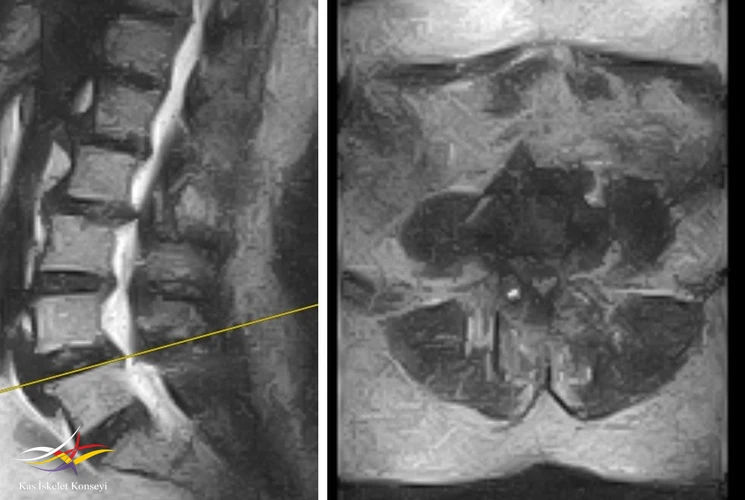

Resim 1. 2029 yılına ait suboptimal MRG de L4-5 listezis ve dar kanal görülmekte.